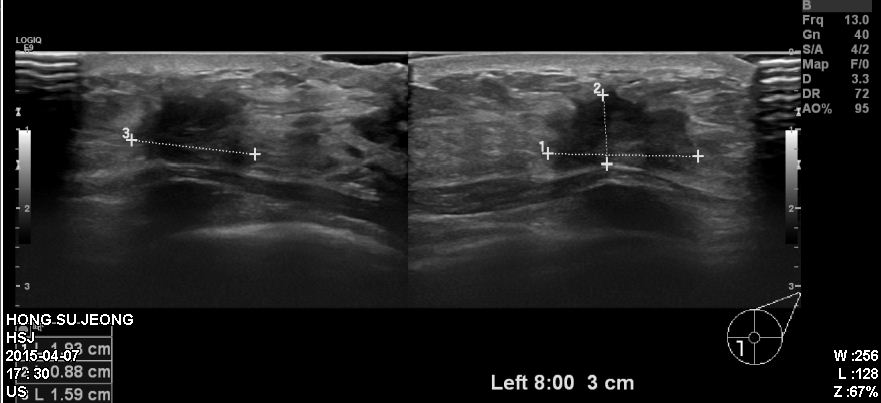

좌측유방에 만져지는 멍우리로 내원하신 30대 환자분이십니다.

본원에서 유방초음파 시행 후 좌측유방 8시 방향에 확인되는 혹을 조직검사하였고

침윤성유관암 진단되었습니다.